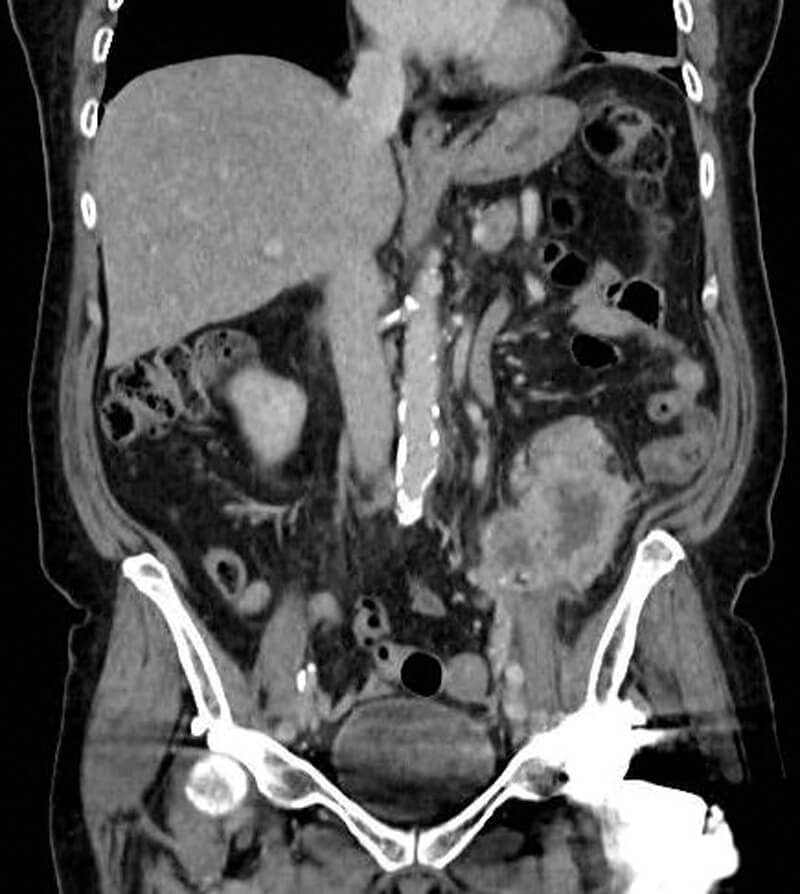

Figure 2: Coronal CT section of upper tract CCUC recurrence.

She re-attended via the emergency department two months postoperatively with left flank pain and significantly raised inflammatory markers. A left-sided 8.3 x 6.5cm retroperitoneal mass with new para-aortic lymphadenopathy was identified on CT abdomen / pelvis and was diagnosed as recurrent disease (Figures 1 and 2). This was engulfing the descending colon and extended inferiorly to psoas. She was treated with intravenous antibiotics and reviewed by oncology but deemed too unfit for systemic oncological treatment in the context of her acute illness. She died three months after her operation.